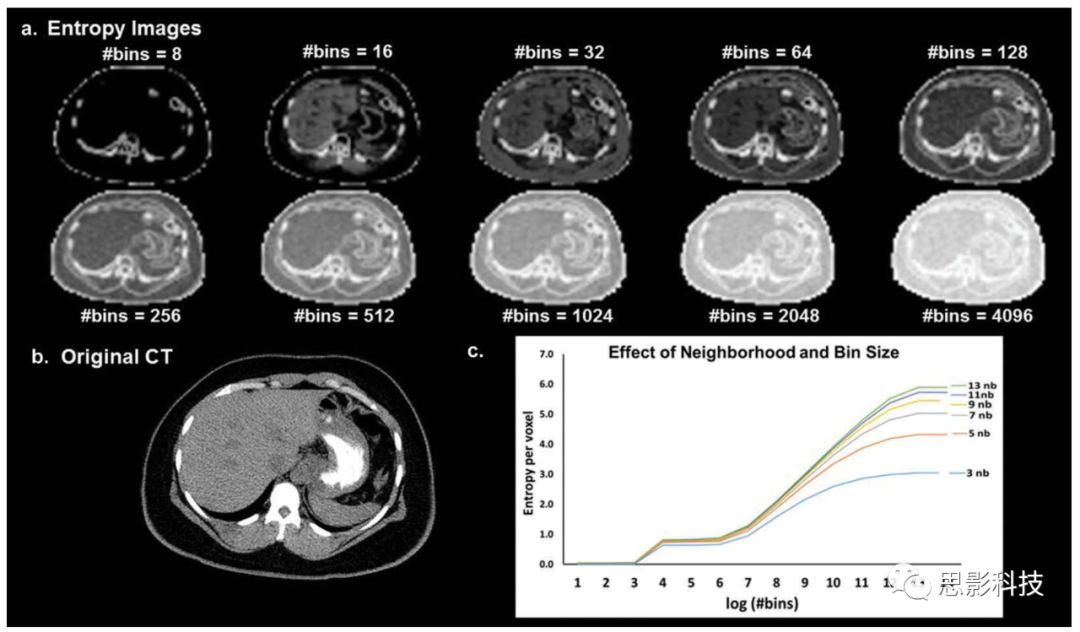

3.2.2 對(duì)圖像合并和灰度級(jí)量化的依賴      用于影像組學(xué)分析的灰度級(jí)或箱數(shù)與相應(yīng)的影像組學(xué)特征之間存在內(nèi)在依賴性。從等式(1)(2)可以看出這種依賴性,其中箱數(shù)用作計(jì)算熵和均勻性的輸入變量。圖10展示了熵對(duì)分箱和用于圖像過濾的鄰域參數(shù)的依賴性。當(dāng)合并增加時(shí),會(huì)導(dǎo)致信息和圖像對(duì)比度丟失。      Shafiqul-Hasan等人評(píng)估了灰度級(jí)量化和GLCM特征之間的依賴性。[108]對(duì)于某些二階特征。作者發(fā)現(xiàn),影像組學(xué)特征與所選特征集的灰度級(jí)數(shù)呈線性、二次或三次關(guān)系。作者進(jìn)一步提出了修正方程計(jì)算不同的影像組學(xué)特征并測(cè)試它們對(duì)不同體模的功效。然而,灰度級(jí)量化實(shí)際上改變了放射圖像中存在的信息。除了數(shù)學(xué)依賴性之外,灰度級(jí)量化和影像組學(xué)特征之間還存在內(nèi)在依賴性,這在任何研究中尚未得到解決。例如,如果我們考慮將放射圖像量化為一個(gè)灰度級(jí)的極端情況,我們將丟失圖像中存在的所有信息。       不能通過數(shù)學(xué)修改影像組學(xué)公式來糾正影像圖像中的這種信息丟失,而是通過選擇最佳數(shù)量的灰度級(jí)來糾正這個(gè)問題。目前,不存在用于選擇灰度級(jí)數(shù)的標(biāo)準(zhǔn)化方法,該灰度級(jí)數(shù)將最小化所得量化圖像中的信息損失。在未來,只有通過標(biāo)準(zhǔn)化選擇最佳灰度級(jí)或一系列理想灰度級(jí)的程序,才能實(shí)現(xiàn)影像組學(xué)的標(biāo)準(zhǔn)化,以跨多個(gè)平臺(tái)使用放射圖像的量化。

10 a)說明用于圖像濾波和圖像合并的鄰域大小的熵值對(duì)ab)的依賴性。CT圖像(軟組織窗口)。(c)熵與箱的曲線似乎遵循一種不同的模式,其中熵值在一定范圍內(nèi)隨箱數(shù)的對(duì)數(shù)線性變化,在該范圍外保持或多或少的恒定。熵的值隨著鄰域?yàn)V波器的大小的增加而一致地增加。